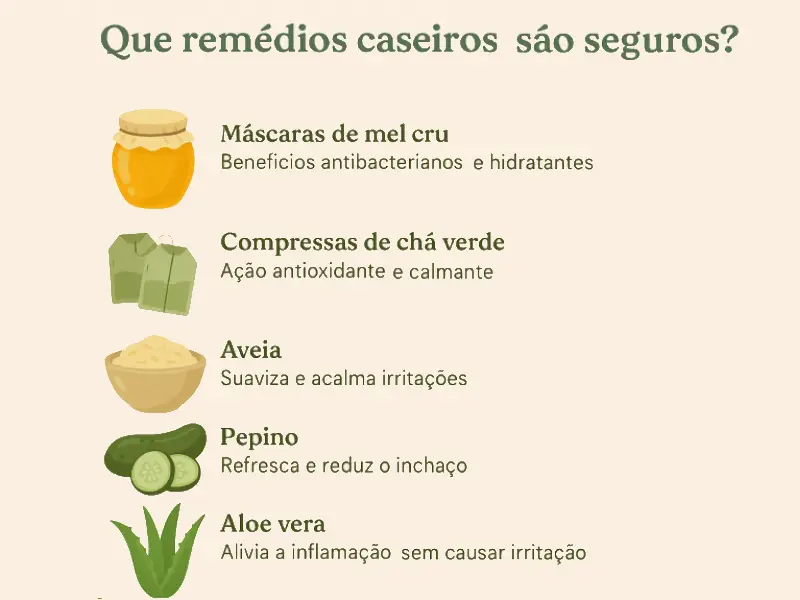

Que remédios caseiros são seguros?

- Máscaras de mel cru: Benefícios antibacterianos e hidratantes.

- Compressas de chá verde: Ação antioxidante e calmante.

- Aveia: Suaviza e acalma irritações.

- Pepino: Refresca e reduz o inchaço.

- Aloe vera: Alivia a inflamação sem causar irritação.

Muitas gestantes preferem explorar opções naturais para tratar a acne durante a gravidez. Embora existam diversos remédios caseiros populares, é fundamental saber quais são seguros. Algumas soluções naturais podem ser eficazes no alívio da acne, mas devem ser usadas com cautela.

O mel é um exemplo de ingrediente seguro e eficaz. Ele possui propriedades antibacterianas e anti-inflamatórias que podem ajudar a acalmar a acne. Aplicar uma máscara de mel pode hidratar suavemente a pele enquanto combate as bactérias causadoras de acne.

Outra opção é o chá verde, que contém antioxidantes poderosos e tem efeitos calmantes. Compressas de chá verde podem ajudar a reduzir a vermelhidão e a inflamação. A Aloe Vera também é conhecida pelo alivio da inflamação.

Para reduzir o inchaço, suavizar a pele sem causar irritações, pode ainda experimentar colocar pepino ou aveia.

Por outro lado, nem todos os remédios naturais são adequados para gravidez. Óleos essenciais podem parecer atraentes, mas alguns podem ser muito fortes ou irritantes.